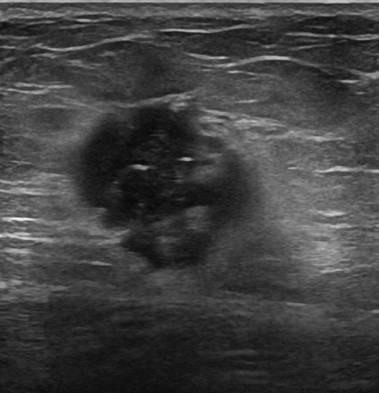

Ung thư vú

» Thông tin: Nữ giới – 51 tuổi.

» Lâm sàng: Khối tuyến vú.